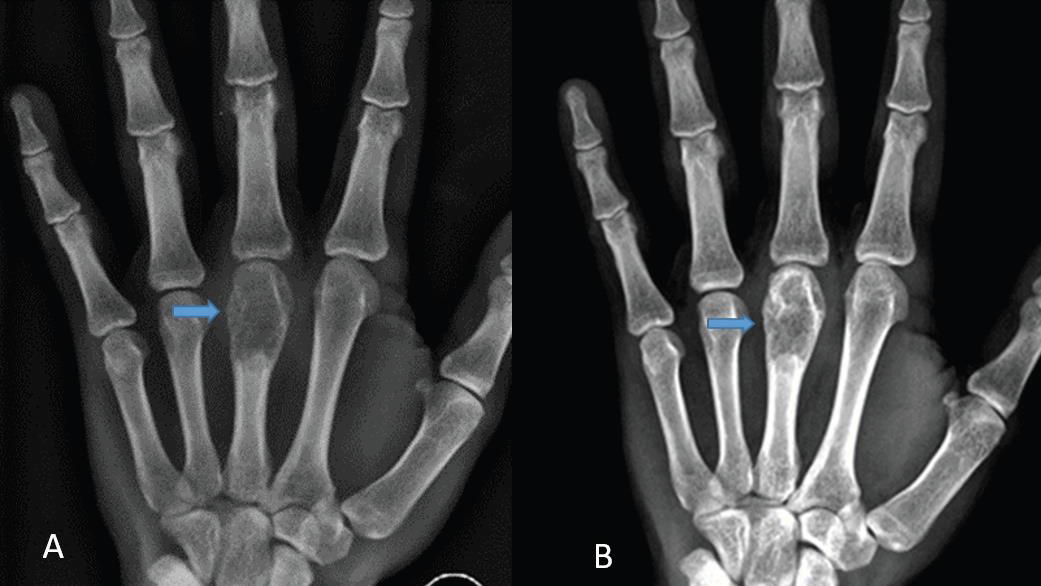

Following the diagnosis, anti-tubercular therapy (ATT) was

initiated. At the six-month follow-up, radiographic evaluation

showed a reduction in soft tissue swelling clinically, a slight decrease

in the lytic component, and increased sclerosis of the lesion [Figure 5].

Figure 5: Before and after treatment, at the six-month follow-up, radiographic

evaluation showed a slight decrease in the lytic component, and increased

sclerosis of the lesion.